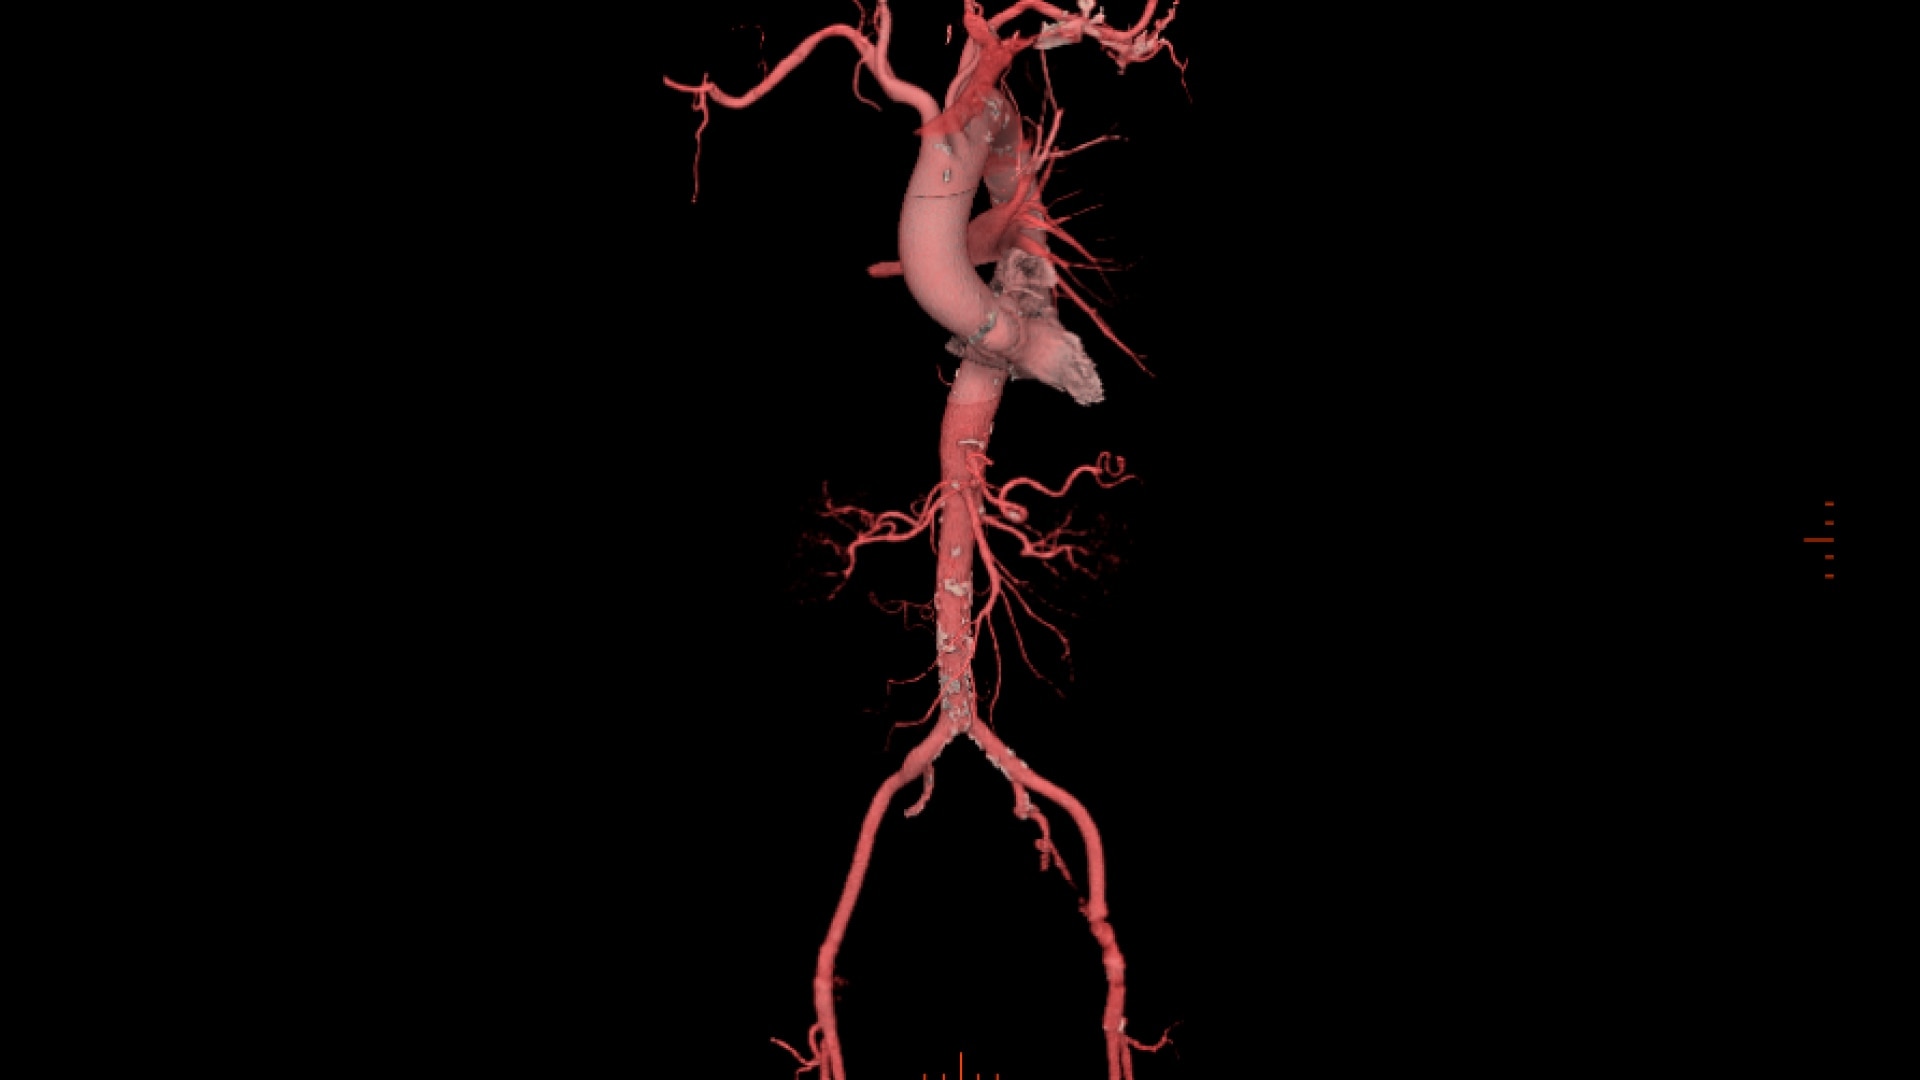

Assess aortic root and plan peripheral access within a single application

• Automatic centerline tracking for peripheral access planning